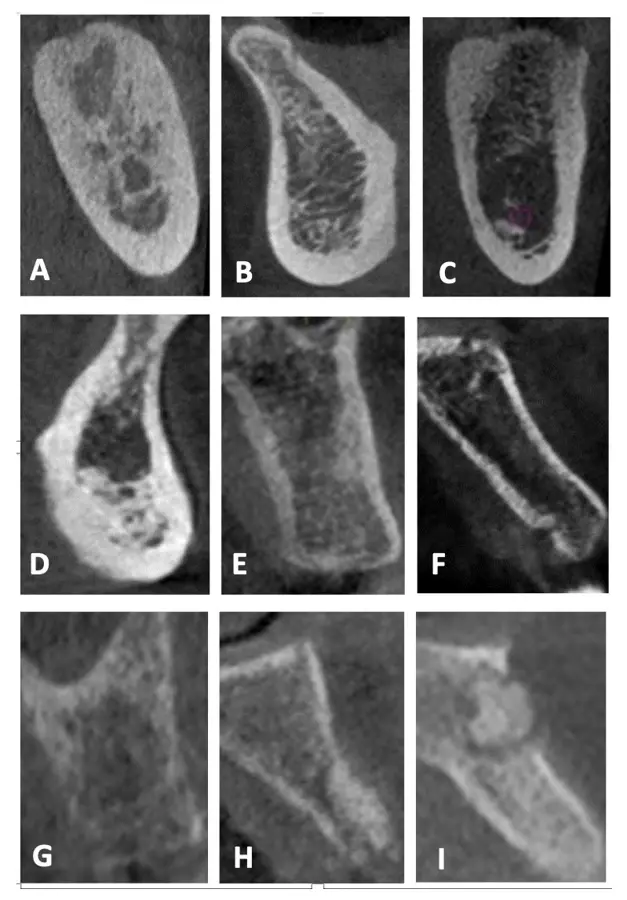

Una reciente publicación de estudios con CBCT propone una modificación a lo anteriormente propuesto por Lekholm y Zarb, que permite sugerir su aplicabilidad para distinguir entre las diversas combinaciones de hueso cortical y esponjoso para definir adecuadamente el tratamiento a fin de optimizar los resultados.17 Esta propuesta se basa en la evaluación de la calidad ósea respecto al grosor de la cortical y a la visibilidad de la cantidad de trabéculas y el tamaño de los espacios medulares en el hueso esponjoso (Figura 4):

- Tipo I: Hueso cortical predominante que rodea al hueso esponjoso de cantidad escasa con trabéculas nítidas en toda la imagen y presencia de espacios medulares pequeños y visibles.

- Tipo II-A: Hueso cortical grueso que rodea al hueso esponjoso de cantidad abundante con trabéculas nítidas en toda la imagen y presencia de espacios medulares pequeños y visibles.

- Tipo II-B: Hueso cortical grueso que rodea al hueso esponjoso de cantidad abundante con predominio de trabéculas difusas en el hueso basal y presencia predominante de espacios medulares amplios y visibles.

- Tipo II-C: Hueso cortical grueso que rodea al hueso esponjoso de cantidad abundante con predominio de trabéculas muy gruesas y nítidas en la basal, con presencia de espacios medulares pequeños y visibles.

- Tipo III-A: Hueso cortical delgado que rodea al hueso esponjoso de cantidad abundante con trabéculas nítidas en toda la imagen y presencia de espacios medulares pequeños y visibles.

- Tipo III-B: Hueso cortical delgado que rodea al hueso esponjoso de cantidad abundante con predominio de trabéculas difusas y presencia de espacios medulares difusos.

- Tipo IV: Hueso cortical difuso que rodea al hueso esponjoso de cantidad abundante con predominio de trabéculas difusas y presencia de espacios medulares difusos.

- Tipo V: Hueso regenerado, de cantidad, visibilidad de las trabéculas y espacios medulares variables.

- Tipo VI: Hueso con patología, de cantidad, visibilidad de las trabéculas y espacios medulares variables.